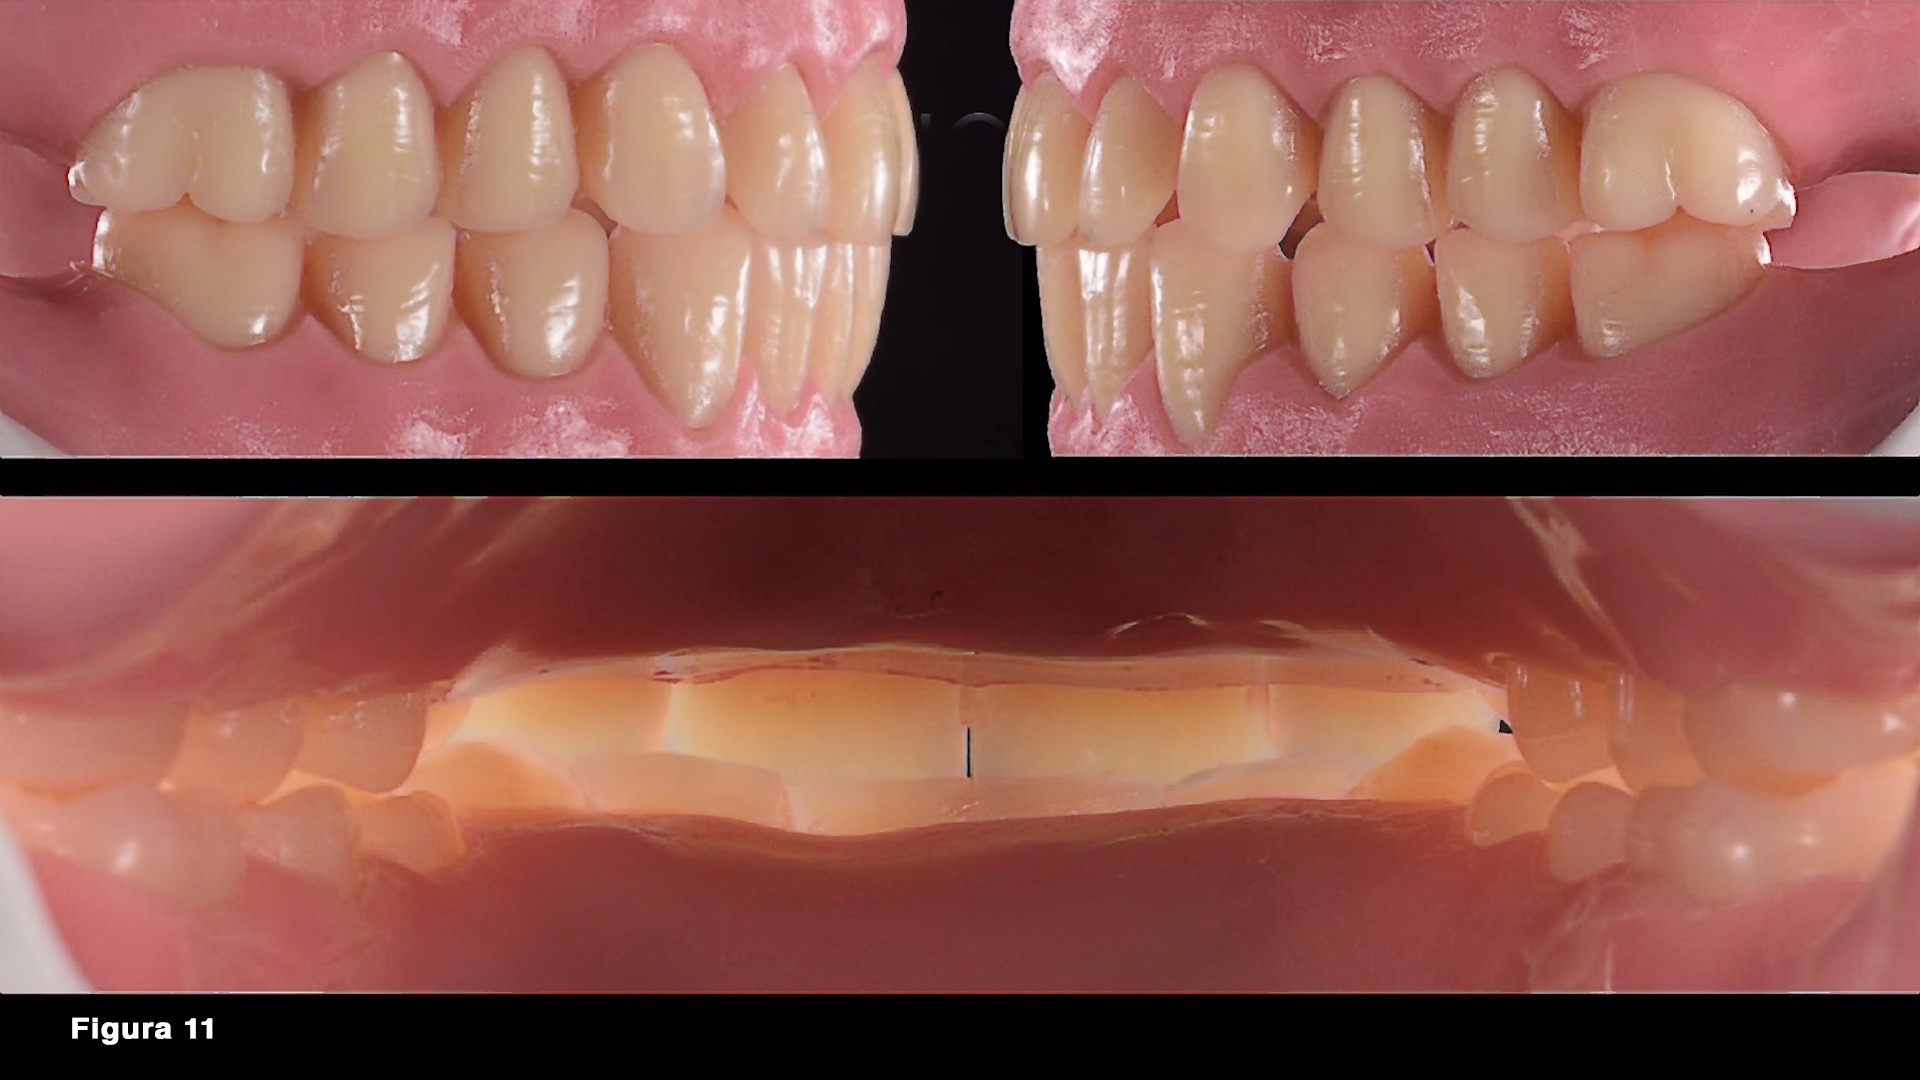

Figuras 10 - 11. Una vez posicionados correctamente los modelos en el articulador, con la información del paciente recogida en el sillón, se inició la fase de montaje y encerado de las prótesis provisionales previas a la extracción, que sea realizaron siguiendo el método del profesor Gerber.

Figuras 38 - 40. La prótesis definitiva se entrega directamente en una cita utilizando y respetando toda la información contenida en la prótesis provisional que el paciente ha podido detectar con el uso.

Figura 41. El resultado en términos de estética y función es satisfactorio y el soporte de la raíz también es adecuado.